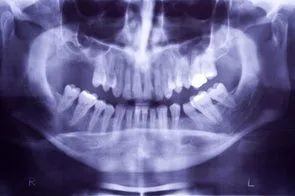

Ridge Augmentation